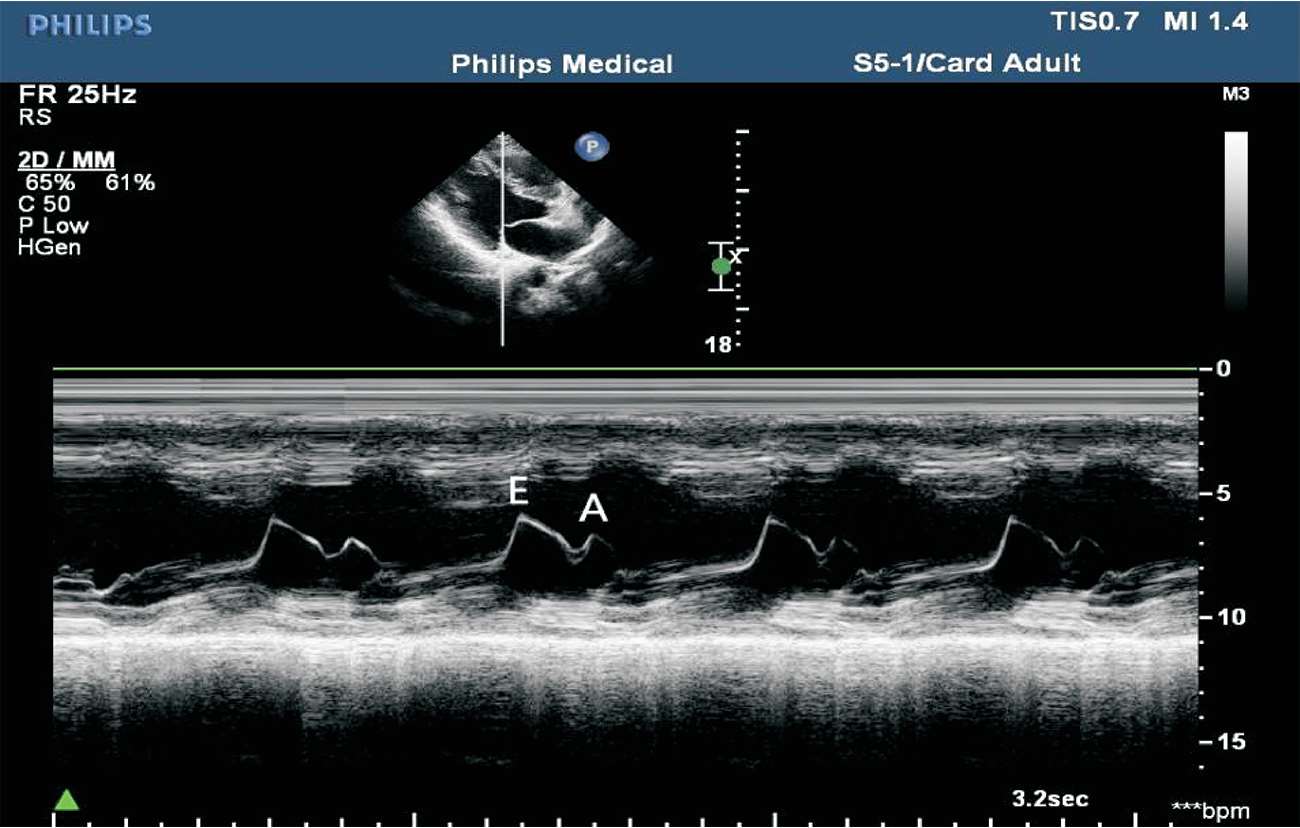

(1)胸骨旁左室长轴切面M型取样线置于二尖瓣瓣尖水平。

(2)结构从前到后依次为右室前壁、右心室、室间隔、二尖瓣前后叶、左室后壁等。

(3)正常二尖瓣前叶曲线为舒张早期E峰和舒张晚期A峰的双峰曲线,而收缩期为一缓慢上升的CD段。

这种双峰曲线具有一定的特异性:A峰位于心电图P波之后,心房收缩推动二尖瓣前叶向前运动。C点位于心电图R波之后,此时心肌收缩,心室压力升高,二尖瓣关闭,产生第一心音。CD段为关闭的二尖瓣随左室后壁的逐渐前移而前移。D点出现于T波与第二心音之后,标准二尖瓣口即将开放。E峰为二尖瓣开放至最大时形成,随后由于左心房排空,左心室充盈,房室间压差迅速减小,二尖瓣前叶曲线迅速下降至F点(见图1-22)。

(4)二尖瓣前后叶活动方向相反,故二尖瓣后叶曲线与前叶曲线相反,呈镜像曲线,为舒张早期E峰和舒张晚期A峰的双峰曲线。收缩期为前后叶合拢形成一起向前的CD段(见图1-23)。

图1-23 二尖瓣波群